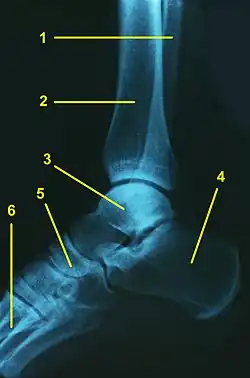

![]() Radiografía lateral de un tobillo normal: 1.Peroné, 2.Tibia, 3.Astrágalo, 4.Calcaneo, 5.Escafoides, 6.Metatarsianos | ||

En la anatomía humana, el tobillo es la articulación donde se unen la pierna y el pie.[1] El tobillo está constituido por tres huesos: el peroné y la tibia que pertenecen a la pierna, y el astrágalo que forma parte del pie. La tibia y el peroné forman conjuntamente en su parte inferior una mortaja articular o cúpula sobre la que se encaja la troclea o polea del astrágalo.[2] El maléolo lateral va a ser más voluminoso que el medial, va a descender más y por tanto, se posterioriza más, lo que explica que exista una ligera oblicuidad (aproximadamente 20.º). Sobre la estructura ósea existe una cápsula fibrosa, un conjunto de ligamentos, músculos y tendones que contribuyen a la solidez de la articulación y hacen posible el movimiento de la misma,[3] es una articulación muy expuesta a lesiones